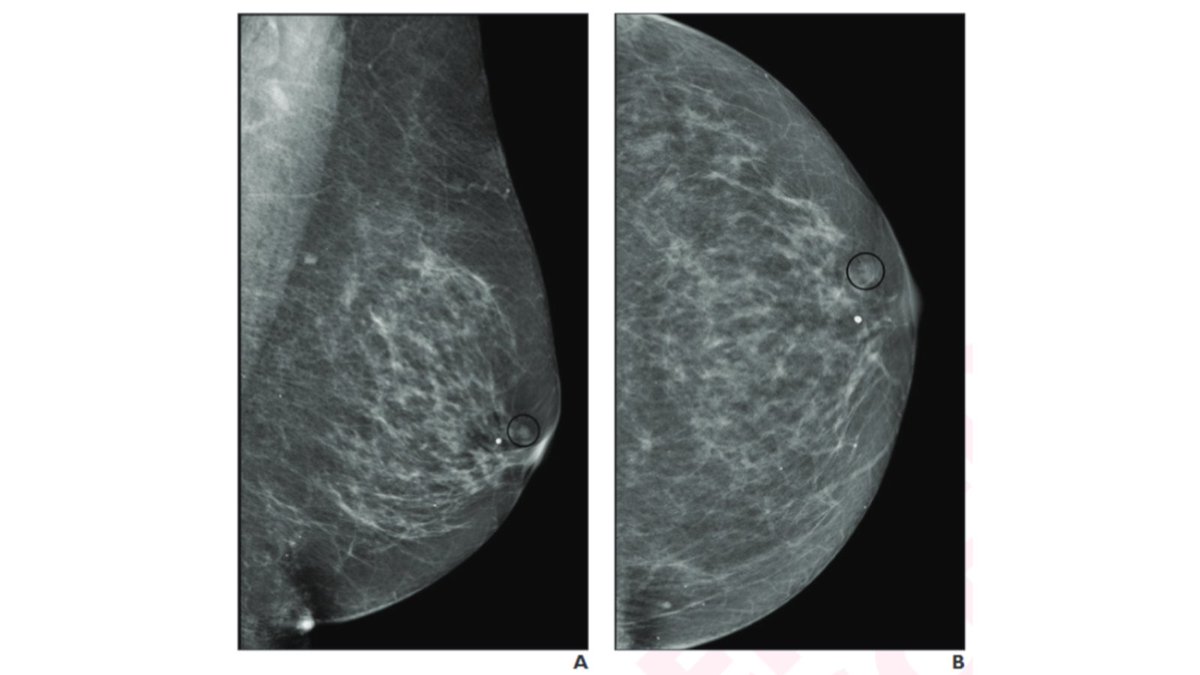

Multimodality Imaging Review of HER2-positive Breast Cancer and Response to Neoadjuvant Chemotherapy Portnow LH et al Breast Imaging doi.org/10.1148/rg.220… @leahportnowmd @SchikarmaneMD #RGphx 2/12